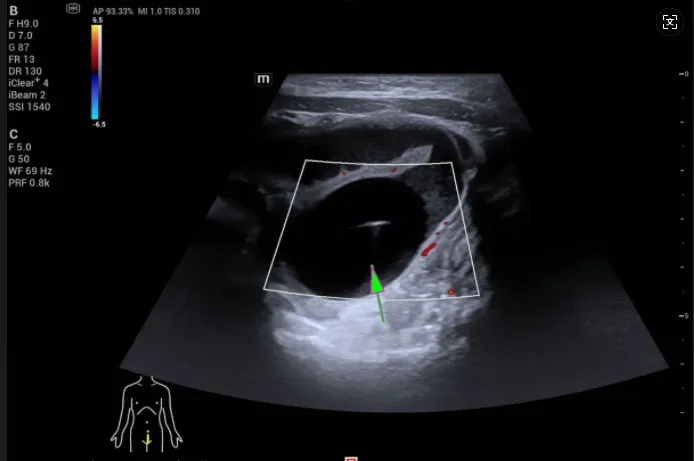

转入深圳市儿童医院后,CT显示,小玥的小肠上段有明显扩张的情况,远端则是正常的干瘪状;而B超则显示,她的腹腔内有一个3.0厘米×2.5厘米的球状物。

经医生诊断,这就是肠梗阻。